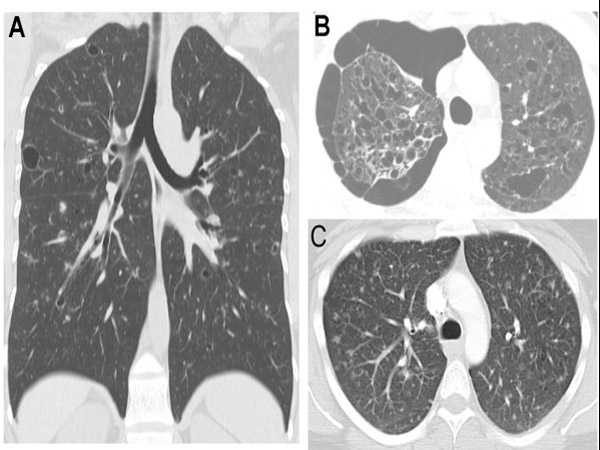

सिटी स्कैन टेस्ट

चेस्ट सिटी स्कैन टेस्ट से पता किया जा सकता है कि आपकी रिकवरी कैसी हो रही है। सिटी स्कैन टेस्ट से लंग फंक्शन रिकवरी के बारे में पता किया जाता है।